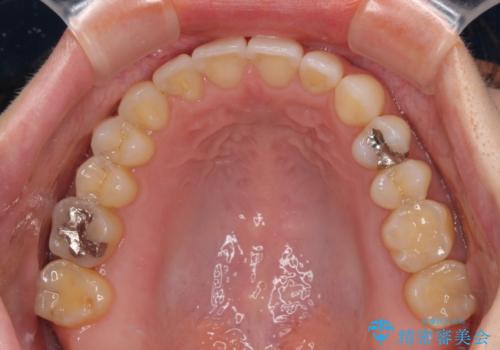

【モニター】狭い上顎歯列とオープンバイト 急速拡大装置を用いた矯正治療

- 前歯の開咬を気にして来院された患者様です。

上顎歯列が狭窄していたため、急速拡大装置により上顎骨を側方に拡大し、その後インビザラインにて矯正治療を行うこととしました。

舌の突出癖が開咬の原因であったので、改善のための舌トレーニングを行っていただきました。

舌トレーニングは後戻りにも大きく影響するため、とても重要なトレーニングです。